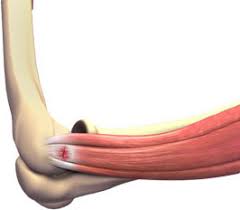

מרפק טניסאים